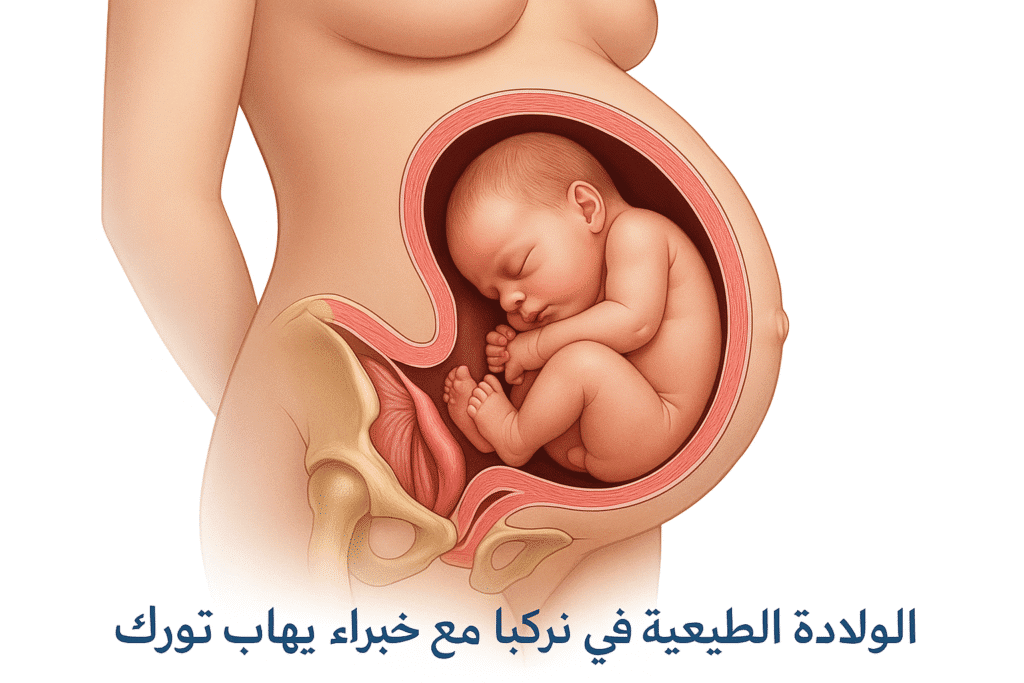

مقالات طبية من مساهمات الأطباء